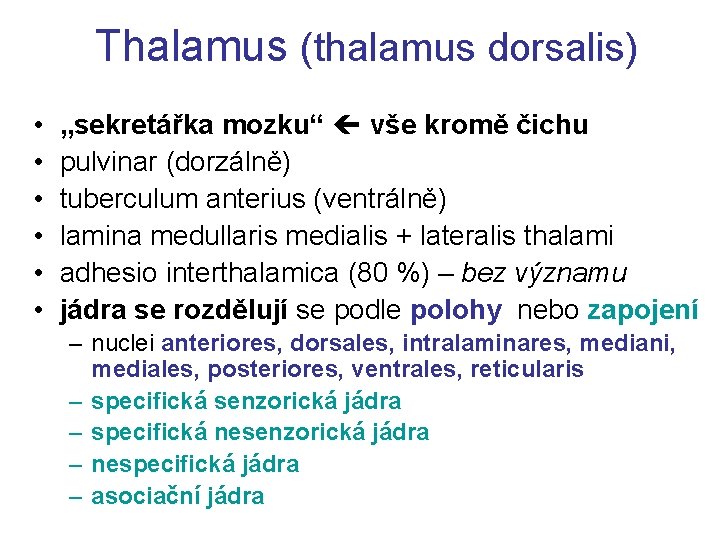

Thalamus (thalamus dorsalis) • • • „sekretářka mozku“ vše kromě čichu pulvinar (dorzálně) tuberculum anterius (ventrálně) lamina medullaris medialis + lateralis thalami adhesio interthalamica (80 %) – bez významu jádra se rozdělují se podle polohy nebo zapojení – nuclei anteriores, dorsales, intralaminares, mediani, mediales, posteriores, ventrales, reticularis – specifická senzorická jádra – specifická nesenzorická jádra – nespecifická jádra – asociační jádra

Třídění thalamických jader dle polohy nuclei anteriores, dorsales, intralaminares, mediani, mediales, posteriores, ventrales, reticularis